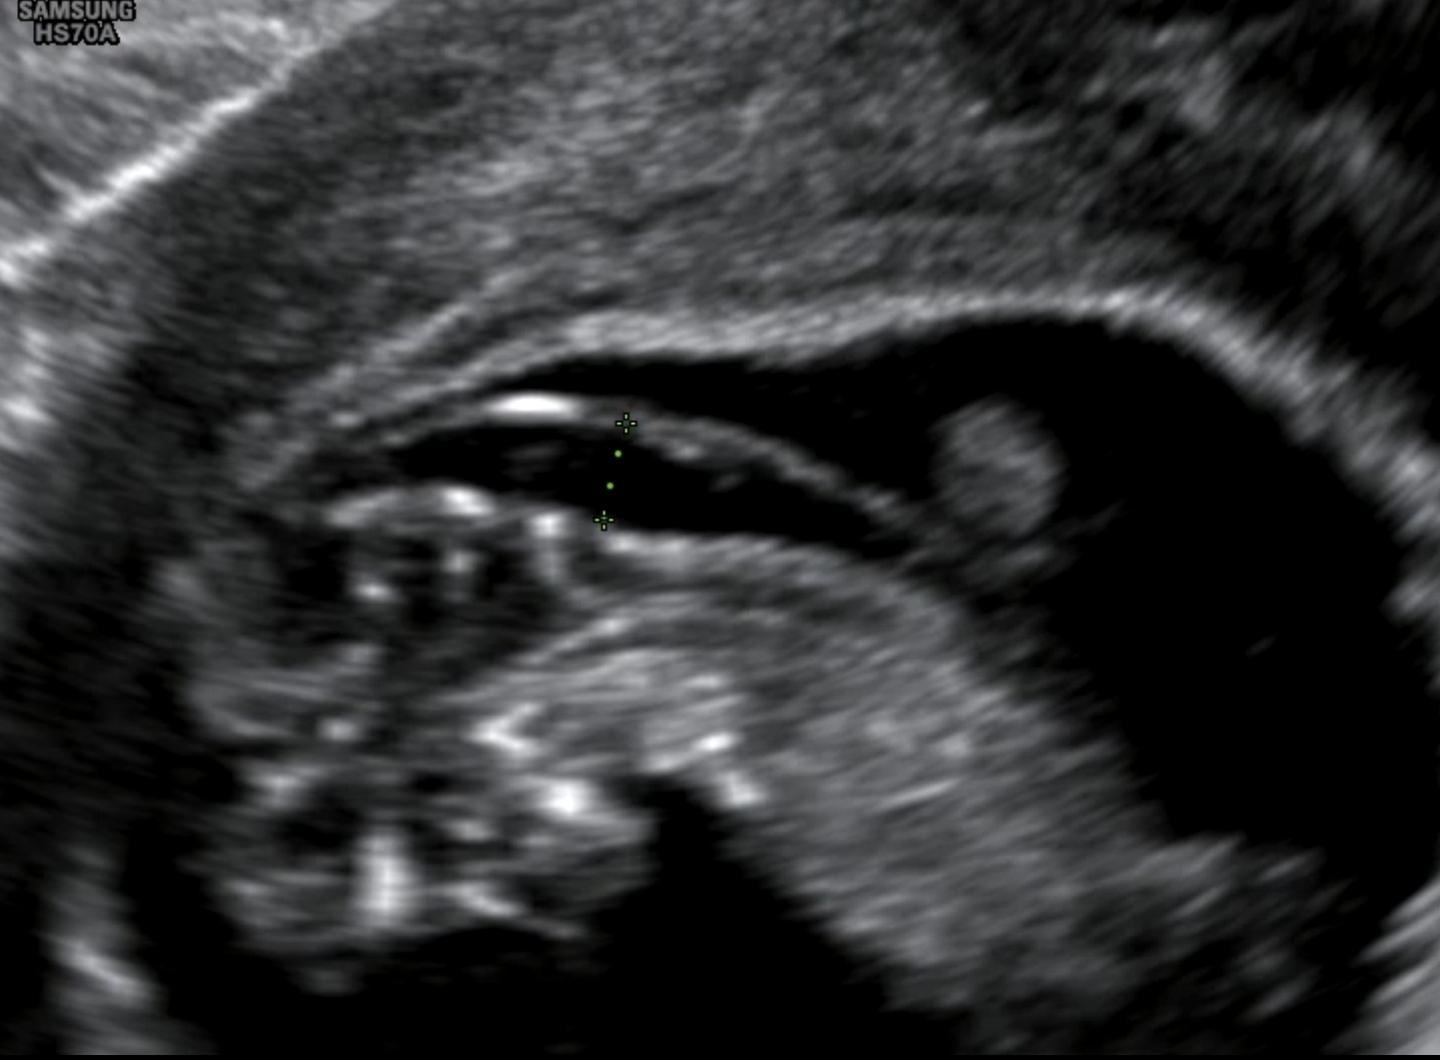

투명대 재는 각도가 이게 맞나요??

약간 대각선같기도하고ㅠㅠ

10주 3일차에 측정된 목투명대 3.27mm는 해당 주수 기준으로는 다소 크게 나올 수 있는 수치이긴 하나, 이 시기에는 표준 평가 시점이 아니어서 해석에 상당한 주의가 필요합니다. 목투명대 검사는 일반적으로 11주 0일-13주 6일, CRL 45-84mm 범위에서 태아 머리와 몸통이 정중앙 시상면에 정확히 놓인 상태에서, 목 뒤 투명층을 피부 경계에 거의 수평으로 측정해야 의미가 있습니다. 제공된 초음파는 태아 자세가 완전히 펴져 있지 않고, 측정선이 약간 대각선으로 보이며 정중 시상면이 완벽히 확보됐다고 보기는 어렵습니다. 이런 경우 실제보다 크게 측정되는 일이 흔합니다.